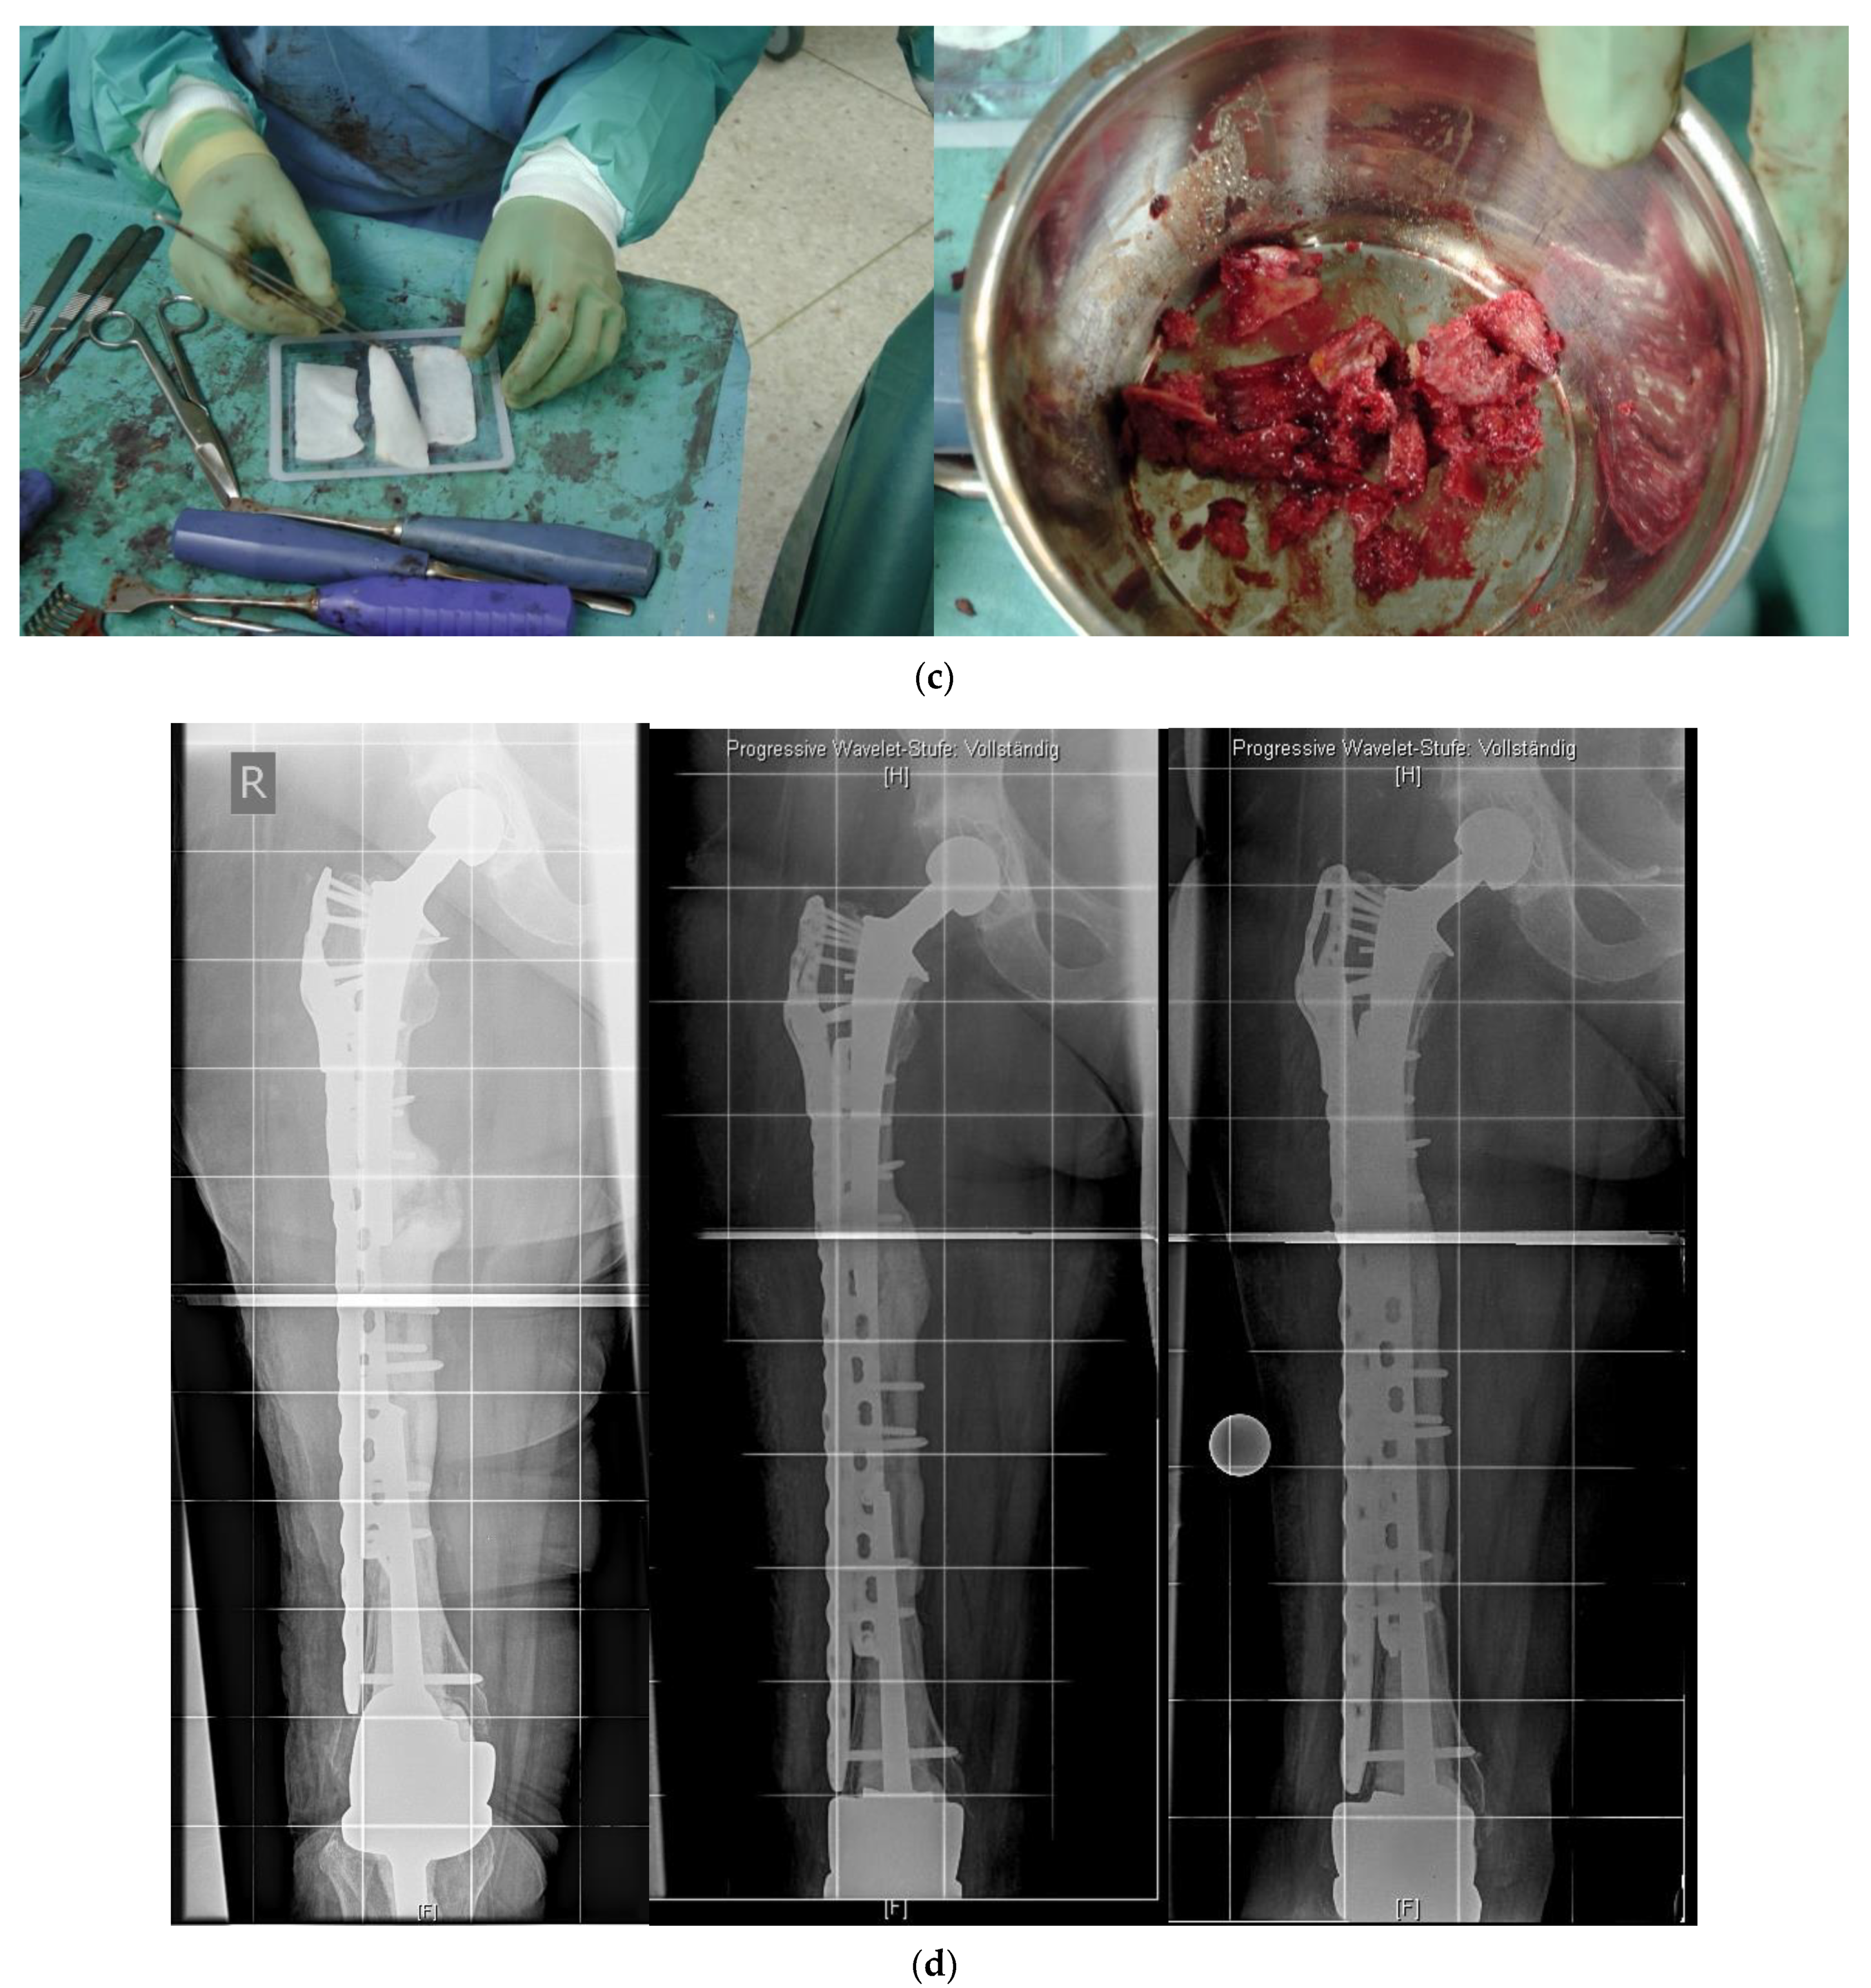

In revision cases and interprosthetic fractures, double plating is an alternative treatment option to avoid high-risk operations such as a total femur replacement. Figure 4 shows a successfully treated hypertrophic non-union after several interprosthetic re-fractures, using double plating in combination with autologous bone-grafting and growth factor application.

Figure 4. (a) Interprosthetic hypertrophic non-union. Intraoperative situs showing the failed plate fixation and the non-union. (b) Intraoperative situs showing the double plating. (c) Double plating combined with bone-grafting and growth factor application. (d) Postoperative follow-up X-rays after 6 weeks, 12, and 24 months, demonstrating complete healing and remodeling of the fracture.